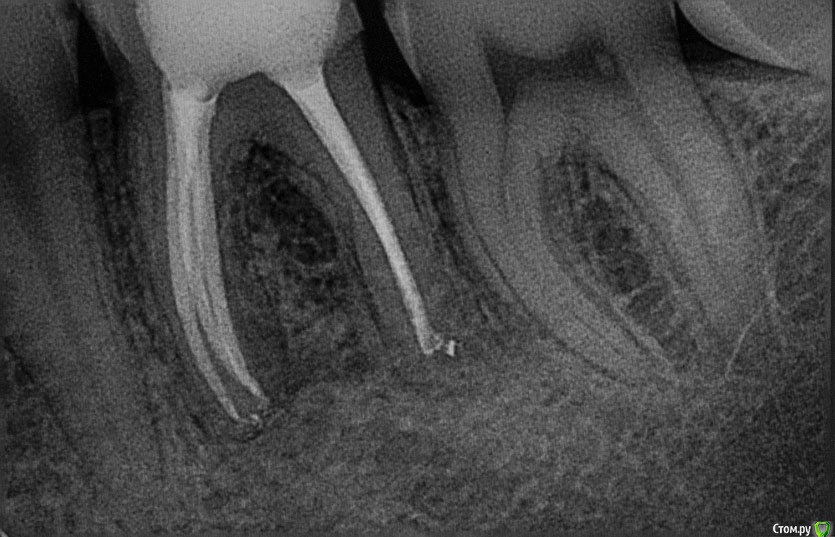

M@estro Опубликовано 3 декабря, 2014 Автор Поделиться Опубликовано 3 декабря, 2014 Мне в увеличении хорошо видно, работала ли апикальная часть инструмента , и с какого размера она работала.По поводу всяких общих рекомендаций - сколько каналов в премоляре ? На "подумать" скину картинку : http://s020.radikal.ru/i704/1412/d1/2eaf7d816fea.jpg 2 Ссылка на комментарий

Гарриевич Опубликовано 19 декабря, 2014 Поделиться Опубликовано 19 декабря, 2014 Мне в увеличении хорошо видно, работала ли апикальная часть инструмента , и с какого размера она работала. По поводу всяких общих рекомендаций - сколько каналов в премоляре ? На "подумать" скину картинку : о-ф-и-г-е-т-ьмне в 3.3 нифига не видно) 1 Ссылка на комментарий

M@estro Опубликовано 21 декабря, 2014 Автор Поделиться Опубликовано 21 декабря, 2014 о-ф-и-г-е-т-ьмне в 3.3 нифига не видно)Ты что,опилки на витках не видишь? Ссылка на комментарий

Гарриевич Опубликовано 27 декабря, 2014 Поделиться Опубликовано 27 декабря, 2014 Ты что,опилки на витках не видишь?)))) убил 1 Ссылка на комментарий